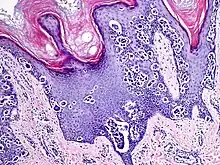

Melanocytic acral nevus with intraepidermal ascent cells (MANIAC)